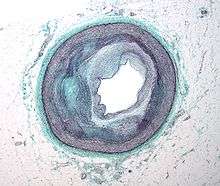

Typically, coronary artery disease occurs when part of the smooth, elastic lining inside a coronary artery (the arteries that supply blood to the heart muscle) develops atherosclerosis. With atherosclerosis, the artery's lining becomes hardened, stiffened, and swollen with calcium deposits, fatty deposits, and abnormal inflammatory cells - to form a plaque. Deposits of calcium phosphates (hydroxyapatites) in the muscular layer of the blood vessels appear to play not only a significant role in stiffening arteries but also for the induction of an early phase of coronary arteriosclerosis. This can be seen in a so-called metastatic mechanism of calciphylaxis as it occurs in chronic kidney disease and haemodialysis (Rainer Liedtke 2008). Although these patients suffer from a kidney dysfunction, almost fifty percent of them die due to coronary artery disease. Plaques can be thought of as large "pimples" that protrude into the channel of an artery, causing a partial obstruction to blood flow. Patients with coronary artery disease might have just one or two plaques, or might have dozens distributed throughout their coronary arteries. A more severe form is chronic total occlusion (CTO) when a coronary artery is completely obstructed for more than 3 months.[46]